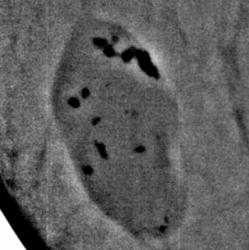

Протокол исследования. В верхнем наружном квадранте инволютивно измененной молочной железы (в годы климакса) определяется тень значительных размеров, овальной формы, средней интенсивности, неоднородной структуры с довольно ровными контурами – фиброаденома. На фоне тени фиброаденомы определяются полиморфные и различные по величине известковые включения. В параареолярной области определяется тень круглой формы средней интенсивности, однородной структуры с ровными контурами – мелкая фиброаденома. Представленные снимки во вложенных файлах (см. ниже). 1 – снимок в прямой проекции; 2 – снимок в боковой проекции; 3, 4 – участки с патологическим образованием, выделенные «навигатором» для более детального анализа. 5- «кальцинат», выделенный навигатором – структура кальцината неоднородная.

Заключение: Инволютивная молочная железы в годы климакса. Фиброаденома крупных размеров левой молочной железы с локализацией в верхнем наружном квадранте с известковыми включениями. Фиброаденома в параареолярной области.